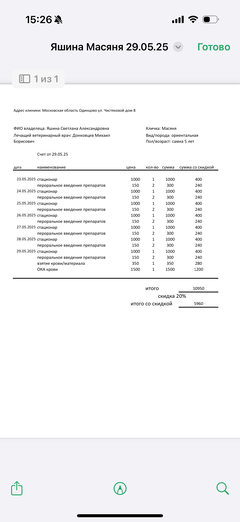

Ярко выраженная болезненность в области крестца, на обезболе полегче. По результатам приема невролога проведена миелография - множественная компрессия, возможно опухоль, возможно грыжа, нужно удалять...

Баланс на 12.06.2025: минус 32 396,34